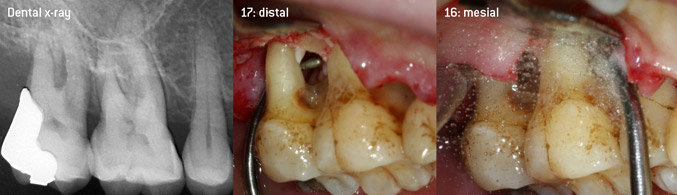

As initiators of the development of the new diamond-coated 3AP air scaler tip, the two dentists recognized the need for improvement of the handling restrictions of the commercially available diamond-coated tips, especially during furcation treatment and when working in tight intraosseous pockets. This should be possible for both non-surgical (Figure 2) and surgical (Figure 3) procedures.

The aim was to develop a universally applicable tip in order to avoid time-consuming tip changes. In addition, it should be easier to use the new working tips in tight intraosseous pockets from distal and at the distal furcation entrance of maxillary molars, allowing more effective use of instruments as a result. This was achieved by employing an instrument curve with a larger diameter (Figure 1), which is highly advantageous for closed debridement on teeth with advanced attachment loss and involvement of furcation in particular (Figure 4).